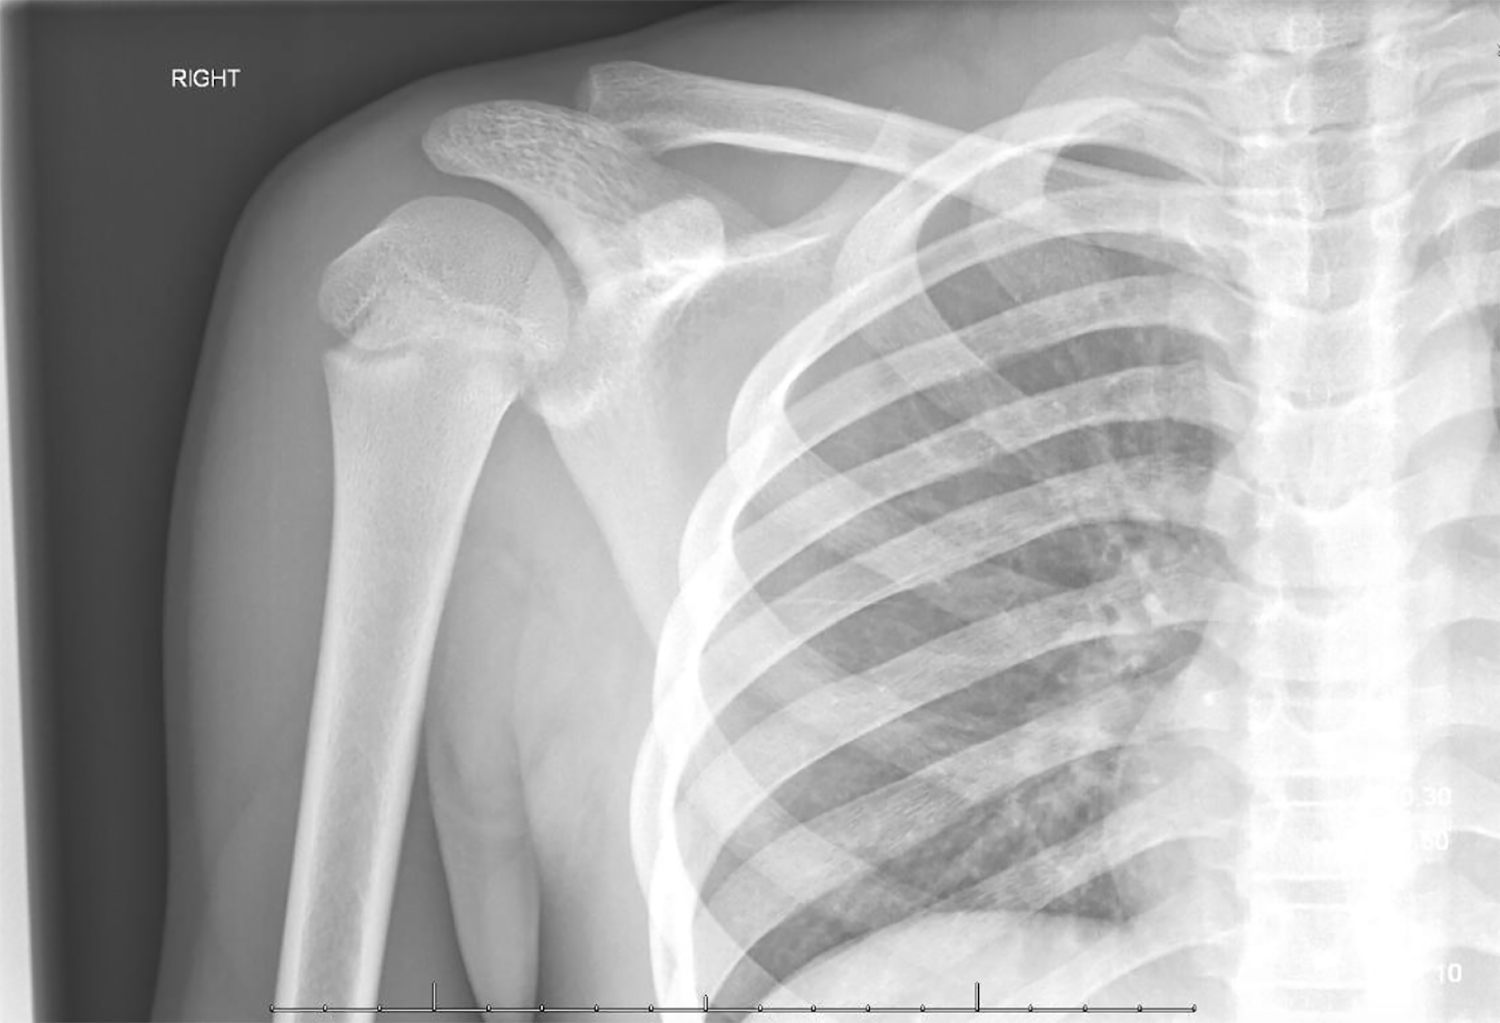

Shoulder Injury Dislocated Clavicle Collar Bone and Stock Photo What Is A Dislocated Collar Bone A fracture is a broken bone, while. A broken collarbone is usually caused by an injury to your shoulder and needs to be treated in hospital. Learn how to identify the signs, types, and severity. Learn about the causes, symptoms, and treatments of shoulder fractures and dislocations, which are common injuries to the shoulder joint. A dislocated collarbone, or clavicle,. What Is A Dislocated Collar Bone.